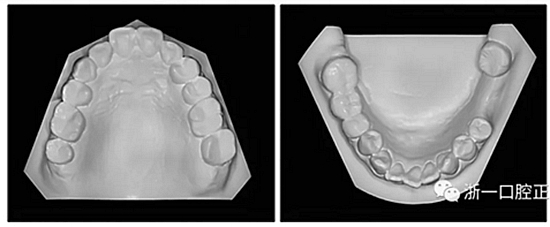

36歲;女性;尋求下頜左后方區(qū)域間隙管理的建議(圖1和圖2),通過治療獲得了良好的牙頜面效果(圖3和圖4)。她被診斷患有骨性I類和代償性牙性II類錯合畸形,并且上頜左側(cè)尖牙缺失(圖1和2)。大約七年前,由于不可修復(fù)的齲齒,拔除了下頜左側(cè)第一和第二磨牙(圖5)。37相鄰的第三磨牙向近中移動并傾斜入間隙,導致無牙頜間隙減小至約14 mm(圖2和圖5)。臨床和影像學評估顯示多發(fā)性齲損和在下頜右側(cè)567處有一不良的固定橋修復(fù)體(圖1和5)。此外,下頜左中切牙缺失,造成下頜中線向左側(cè)偏移約3 mm(圖1和圖2)?;颊咦栽V,她的右上第一前磨牙和左上尖牙在13歲時由其家庭牙醫(yī)拔除,因為它們被阻塞到頰側(cè)萌出(圖1)。上頜第二磨牙缺失(未知病因),并且相鄰的第三磨牙已經(jīng)轉(zhuǎn)移到第二磨牙間隙中。如補充材料所示,美國正畸學差異指數(shù)DI是28分。種植體部位(下頜左側(cè)和右側(cè)第一磨牙)由于復(fù)雜性得到額外4分(補充材料)。

圖2. 治療前牙齒模型